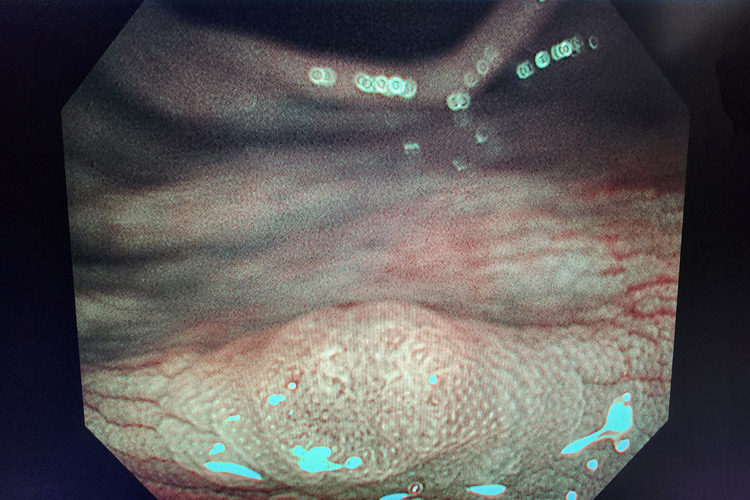

診断にあたっては主に大腸内視鏡検査が行われ、ポリープの有無を確認し、見つかった場合はその大きさ・形状・色調などを観察します。精確なポリープの性状診断は、顕微鏡を用いた病理組織学的検査によって行われます。